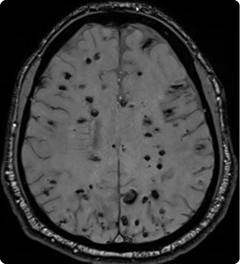

| Quest | Point of care genetic diagnostics in neurology |